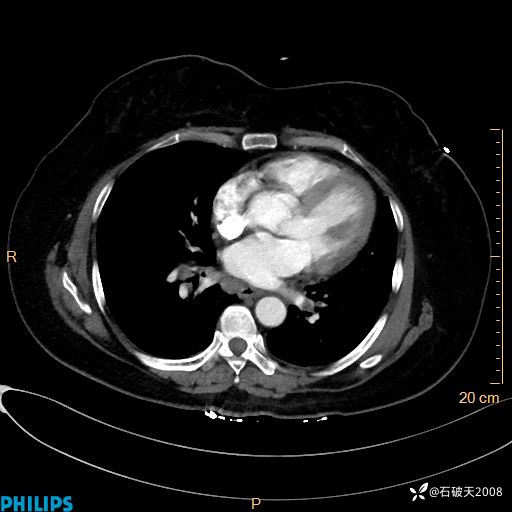

肺结节病?纵膈型肺癌?淋巴瘤?有点意思,欢迎围观

女 52岁 主 诉:咳嗽10余天,咳痰2天。

现病史:10余天前无明显诱因出现咳嗽,呈阵发性干咳,伴咽喉部发痒,无咽痛,无咳痰,无鼻塞、流涕、打喷嚏,无发热、畏寒、寒颤,无头痛、头晕,无胸闷、胸痛,无反酸、烧心,无腹痛、腹泻,无尿频、尿急,无皮疹等,在当地诊所求治,给予口服药物治疗(具体不详),病情无好转。遂在当地社区卫生服务中心开具口服药物治疗(具体不详),疗效欠佳。2天前出现咳痰,在我院门诊求治,行胸部CT提示肺部感染,建议住院,患者要求口服药物治疗,目前仍咳嗽、咳白色粘痰,白天量多,夜间自觉喉部喘鸣音,遂再次来院就诊,以“肺部感染”为诊断收入院。发病以来,神志清,精神可,饮食可,夜间睡眠差,大小便正常,近期体重无明显变化。

静脉期